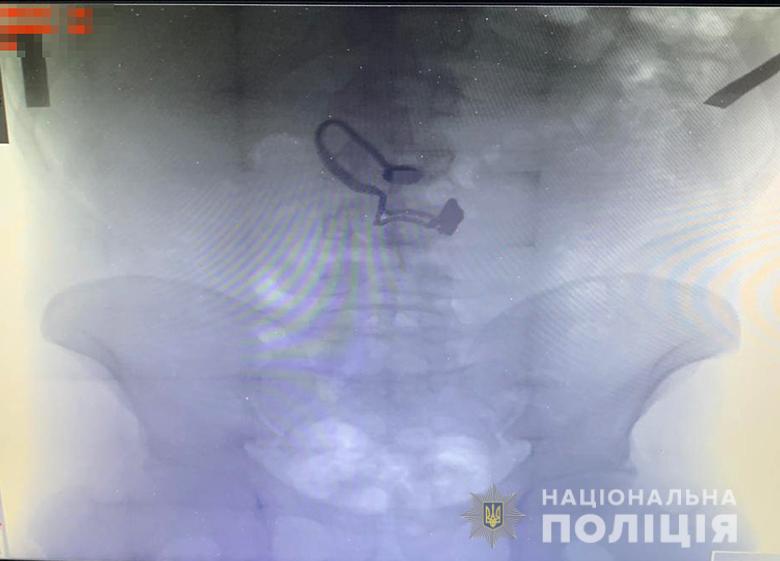

В Киеве задержанный грабитель проглотил сорванную с шеи женщины цепочку

Грабителем оказался 26-летний житель Луганской области, ранее уже судимый за кражи. Его задержали. Во время поверхностного осмотра у мужчины нашли кошелек потерпевшей. Позже он признался полицейским, что сорванную цепочку проглотил.

"Во время медосмотра на рентген-снимке задержанного врачи обнаружили украшение", - сообщают в полиции.